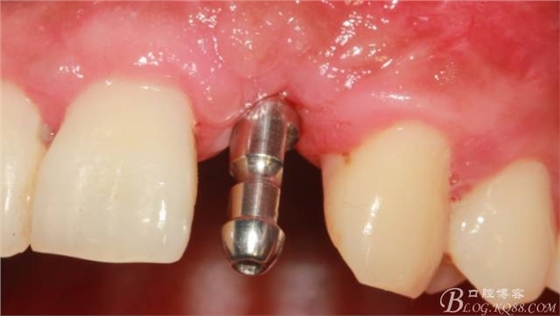

植入植體。

縫合。

術(shù)后X光片。